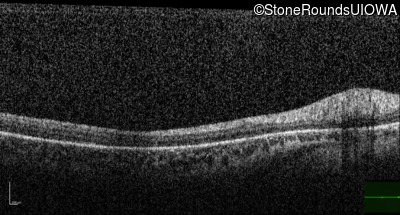

Optical Coherence Tomography - Left - 10/100 -1

Exemplar / OCT Stack